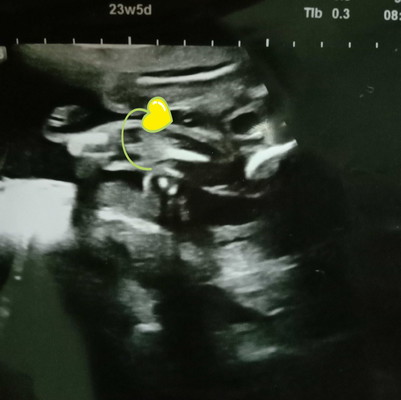

Hi Mommy,,Ni scan sewaktu dlm 5 bulan mcm tu do Klinik swasta,nurse cakap Tak nampak laki ke perempuan..Ade ke mommy2 yg bolej tengok..doc time tu pun sekejap je scan tengok gender,,x sampai brp min pun,kot mommy tahu atau Ade yg lebih kurang mcm sy ke.. Thanks mommy